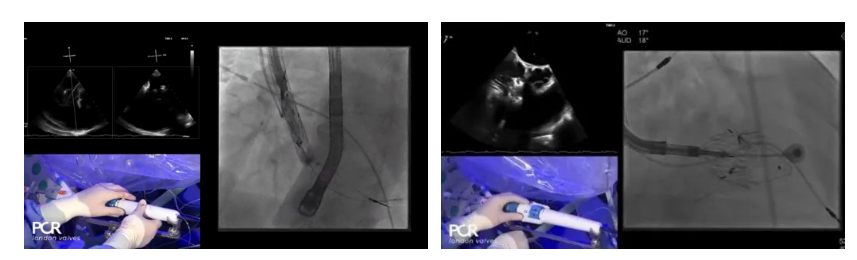

手術在全麻狀態(tài)下開展,采用經(jīng)右側頸靜脈入路的方式將輸送器送入患者心臟內(nèi),在TEE及DSA引導下調(diào)整輸送器頭端角度,使得輸送器與三尖瓣瓣環(huán)平面垂直。在輸送器進入右心室后釋放室間隔錨定裝置,而后釋放瓣葉夾持件(2個耳片結構)成垂直狀態(tài)。在TEE及DSA確定夾持件固定至三尖瓣葉根部且位于右室側后釋放人工瓣心房側盤片。隨后調(diào)整瓣膜同軸性以及室間隔錨定件位置(貼合室間隔),前推藏針管并固定,進而釋放室間隔錨定裝置,并再次確認瓣膜位置、穩(wěn)定性及同軸性,合攏輸送鞘后撤出輸送器,完成LuX-Valve Plus人工三尖瓣瓣膜的植入。